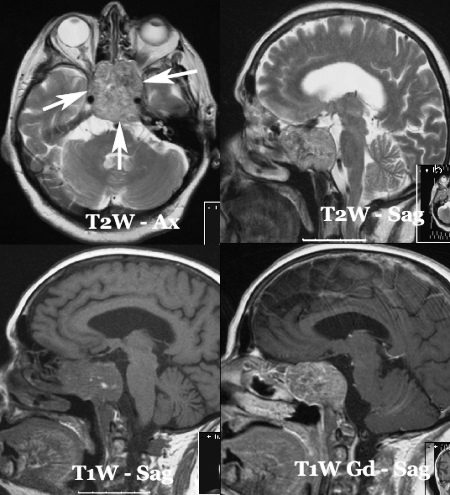

tumor.jpg